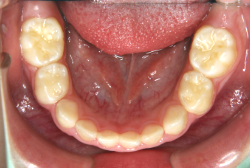

凸凹な歯並びのことを叢生といいます。矯正歯科に来院する患者様の主訴の中で、最も多いのが「配列の凸凹を真っ直ぐにしたい」というものです。歯の大きさと顎の大きさの調和がとれていないことが原因です。

凸凹を主体としたケースの場合、当院の平均治療期間は18ヶ月ですので、このケースは少し長めに経過しました。理由の一つは凸凹の程度がかなり重症だったと言うことですが、もう一つは、右下第2大臼歯が45度くらい前傾していたため、それを整直化させるために時間を要したと考えています。いずれにしても最終結果は大変よい状態と思います。

治療前は並びが乱れて見た目が悪いというのはもちろん問題ですが、歯科医学的に一番困るのは噛み合わせが悪いという点です。上下の犬歯(3番目の歯)は、上下的に離れた位置にあるため接触することができません。つまり歯としては存在していても、歯としては機能していないということです。